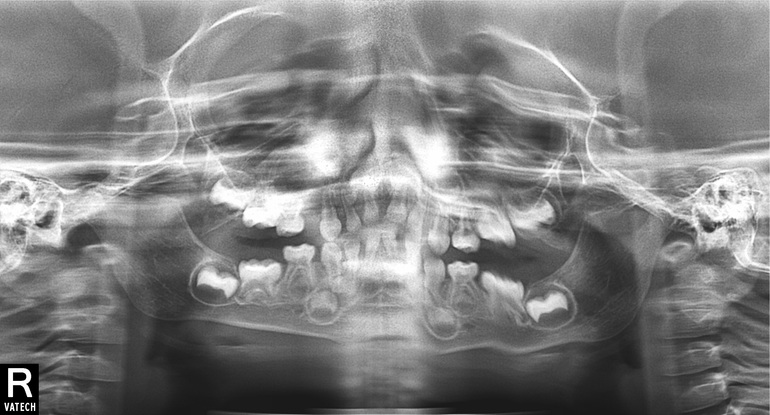

Сходили в субботу на прием в планую клинику, там нам сделали прицельный снимок. Сказали, что это лезет пятерка, а вылезший зуб - это следующий. (у нас такое уже было, что зубки прорезались не по порядку). Сказали, что ничего страшного нет, лечить это не нужно.Но зуб лезет не правильно, под углом, коронкой в щеку. Так же врача смутило, темное пятно между прорезающимся зубом и резцом. Отправила нас на панорамный снимок, после сказала, что они не информативны и нужно еще раз приехать, делать прицельные. на панорамных снимках картина примерно та же, (могу переслать если нужно). Только я белых точечек там не увидела. Только темное пятно.

На приеме говорила что то, что это может быть киста, или какие скопления закладки зубов, я не очень запомнила термины. Очень волнуюсь по этому поводу.